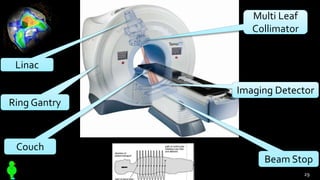

HelicalTomotherapy

continue…,

Linac

Ring Gantry

Couch

Multi Leaf

Collimator

Imaging Detector

Beam Stop

29